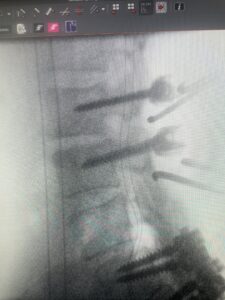

This 61-year-old female with a history of severe osteoporosis and a prior history of a laminectomy from l2-S1 with an L5-S1 instrumented fusion, presents with progressive low back pain and right lower extremity radiculopathy. MRI revealed a grade 1 L2-3 spondylolisthesis with severe stenosis mainly from severe right L2-3 facet joint hypertrophy which was compressing the right L3 descending nerve root. (Fig. 1). She had failed conservative management consisting of physical therapy and pain management with epidurals. She underwent an L1-3 revision laminectomy where we had to dissect a plane underneath the inferior aspect of the L2 lamina. We performed an instrumented fusion at L2-3 with special hydroxyapatite-coated screws to improve fixation to surrounding bone given here severe osteoporosis (Fig. 2) This worked out well and the patient had an uneventful recovery with relief of her leg pain.

Fig: 2a: AP and lateral intraoperative fluoroscopic images demonstrating good placement of L2-3 pedicle screws

Fig. 2b